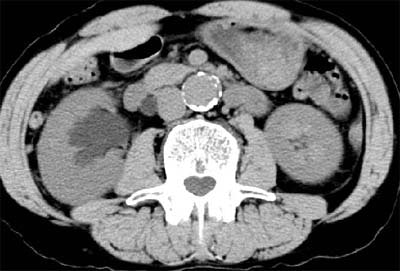

At least a third of his screening clients have HMO coverage, Brant-Zawadzki said, displaying an image of a patient with back pain that had not been prolonged or severe enough to warrant a CT scan from the managed care plan. The diagnosis was hydronephrosis and bladder cancer.

| Above and below: Bladder cancer is detected in a 67-year-old male CT screening patient who presented with back pain. Images courtesy of Dr. Michael Brant-Zawadzki. |